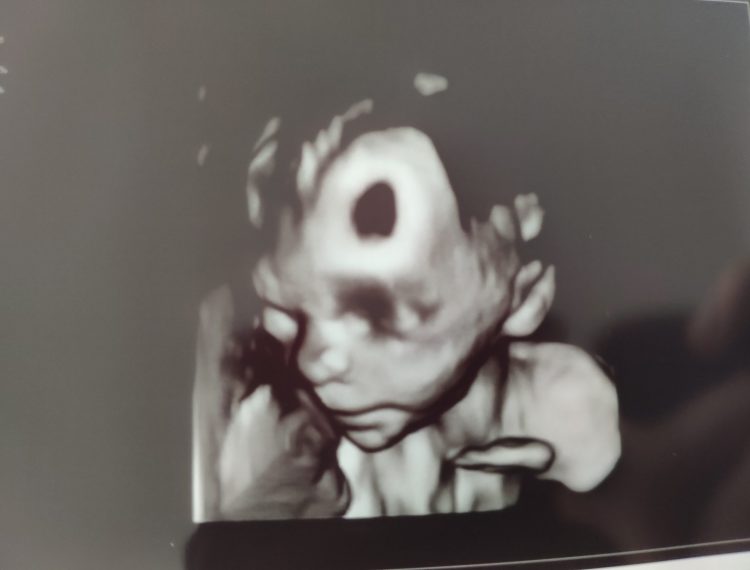

Neues Schwangerschafts-Update gefällig? Vermutlich nicht, oder? Überall auf der Welt sind die Frauen schwanger und posten millionenfach ihre kaum erkennbaren Ultraschallbilder und quatschen über brennende Brüste, Übelkeit, pickelige Haut und Ausfluss – gähn! Ich mach da jetzt einfach mal mit. 😀… Weiterlesen